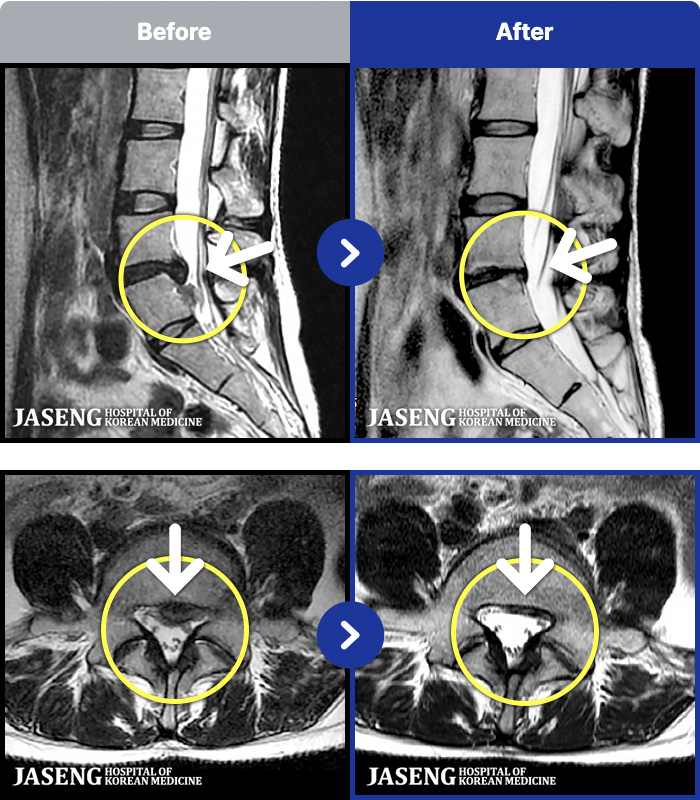

MRI ġ

1,237 MRI ũ ʸ Ȯϼ.